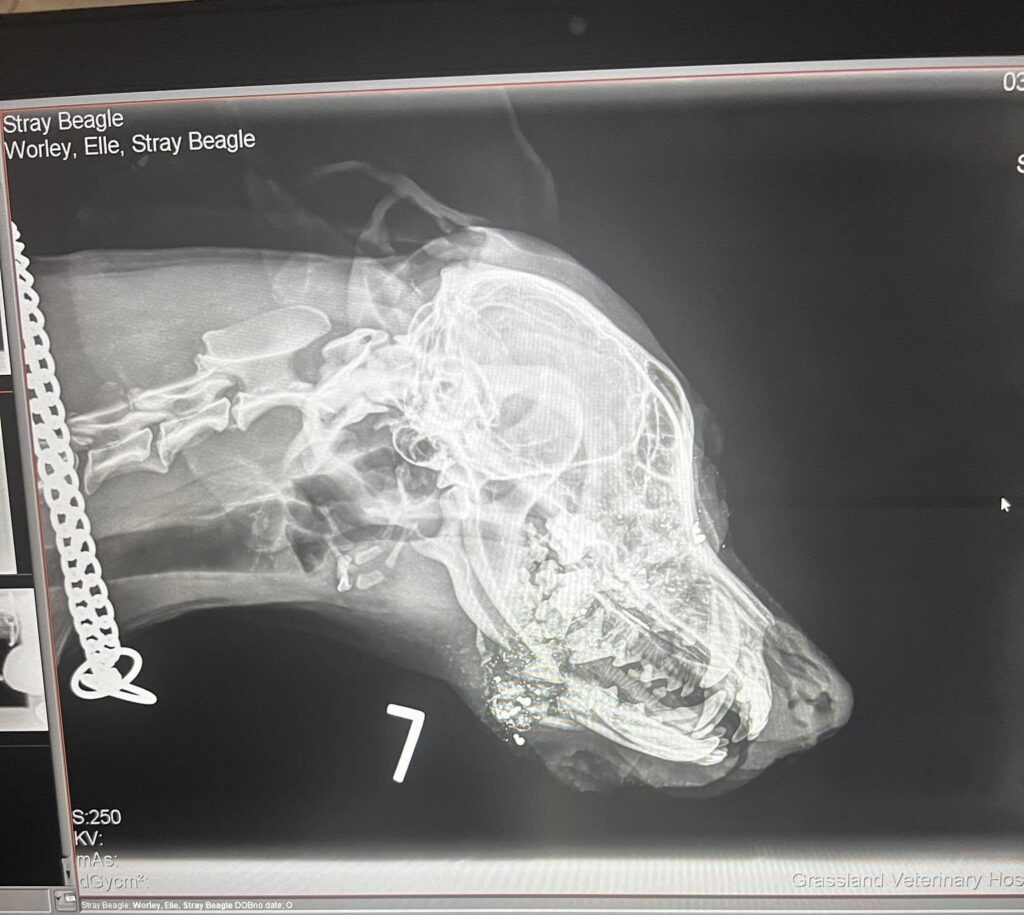

A trip to the veterinarian in Broken Bow a short time later revealed that Juni had been shot in the head and that the right side of her jaw was shattered.

After a referral to a dental and oral surgeon in Omaha and a drive that began at 2:30 AM the next morning, what Juni had experienced became clearer: two shots with a .22 caliber bullet had missed her brain and eye by just centimeters.

Under anesthesia, more extensive x-rays were completed and Juni’s jaw was cleaned out but a reconstruction couldn’t be done that day. The little dog needed time to heal.

“Because of the gunshot wound, the teeth lost blood flow. So we don’t know if we’ll have to extract the teeth, again a wait-and-see scenario. There was also some fragmentation that was in her nasal cavity that the vet said worst case scenario could cause chronic infections but obviously we hope that that’s not the case,” Worley explained.